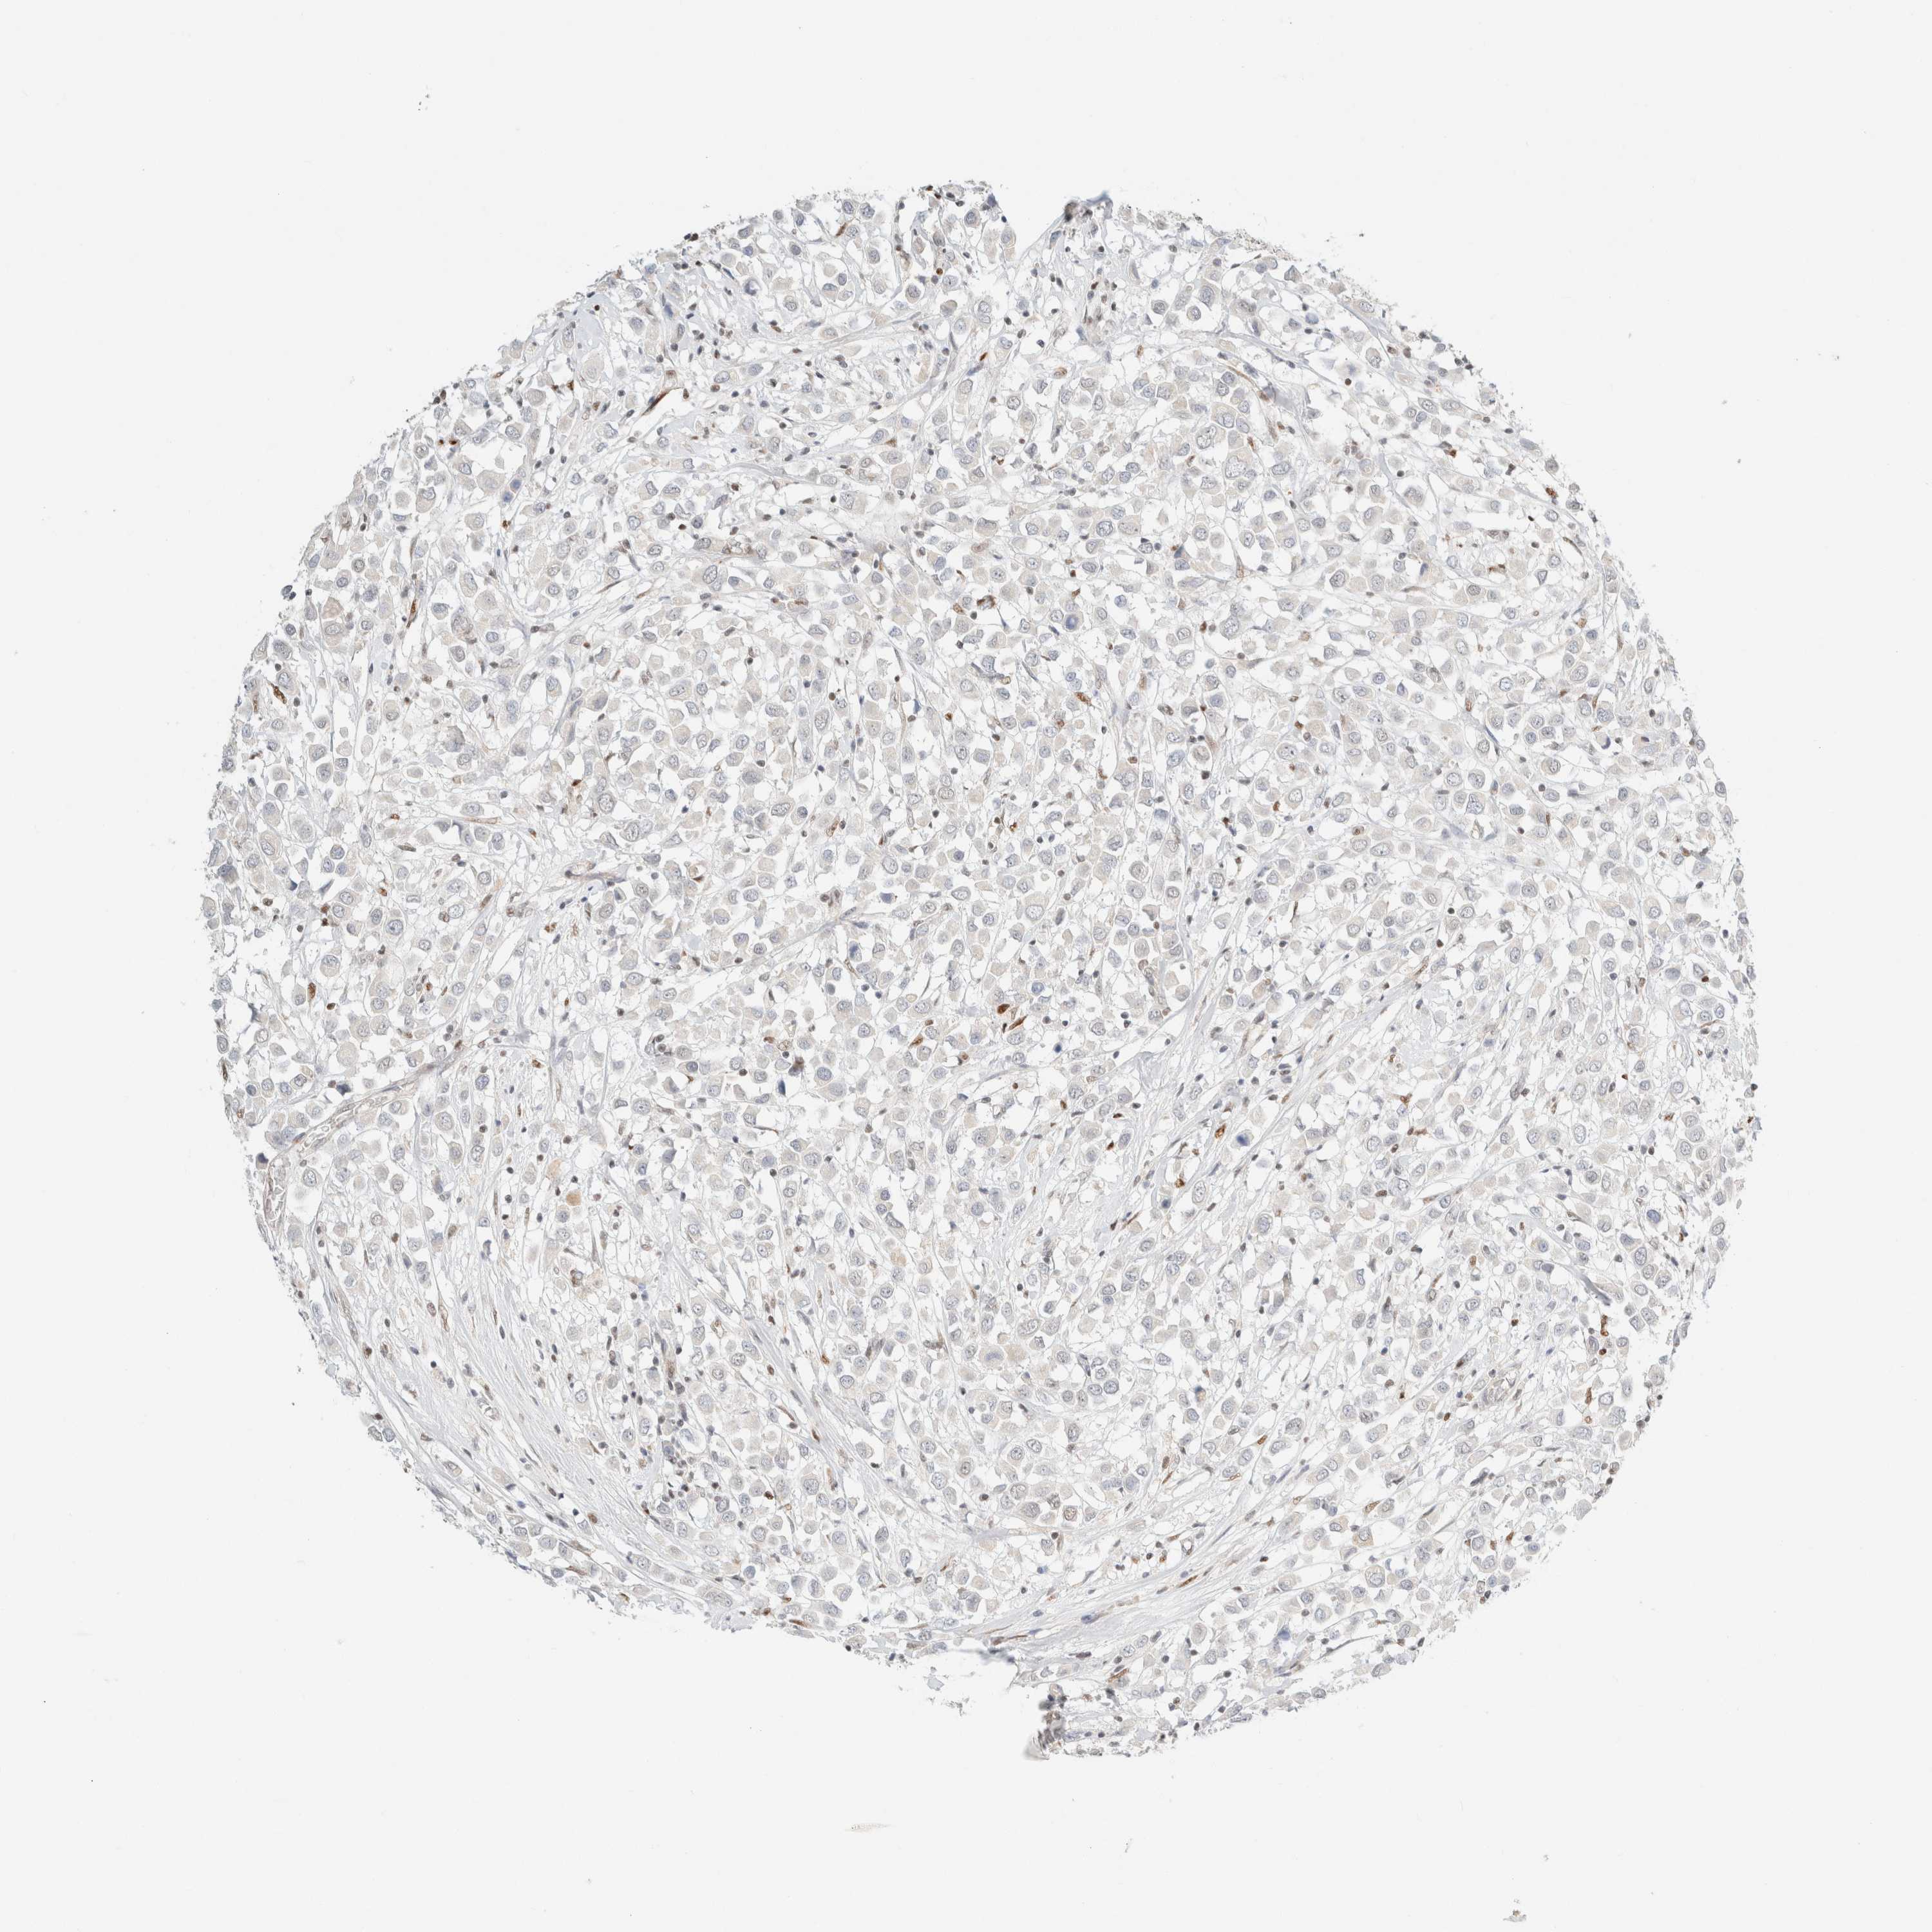

BRCA TCGA BRCA VALIDATION PROTEIN EXPRESSION